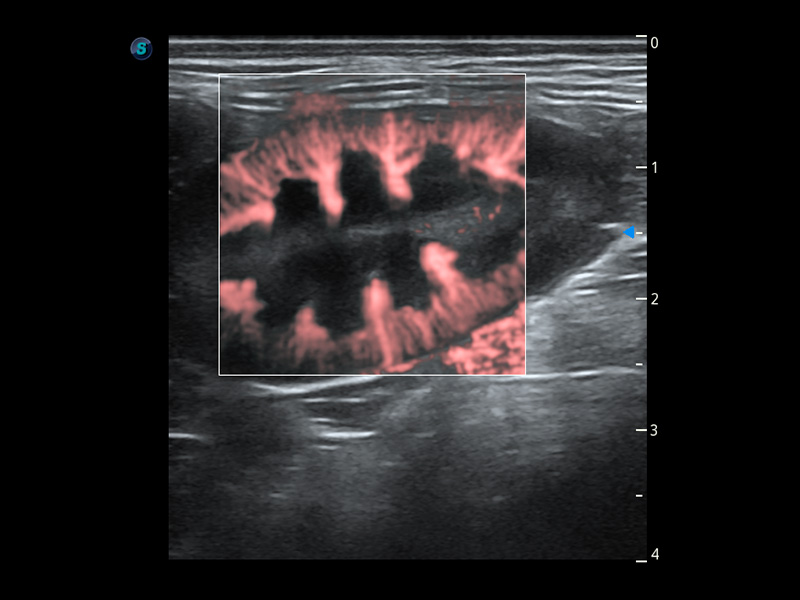

PDI 能量多普勒血流

提供高灵敏度和空间分辦率的血流图像,获得更加真实和丰富的诊断信息。

优异的基础图像

(猫)膀胱结晶